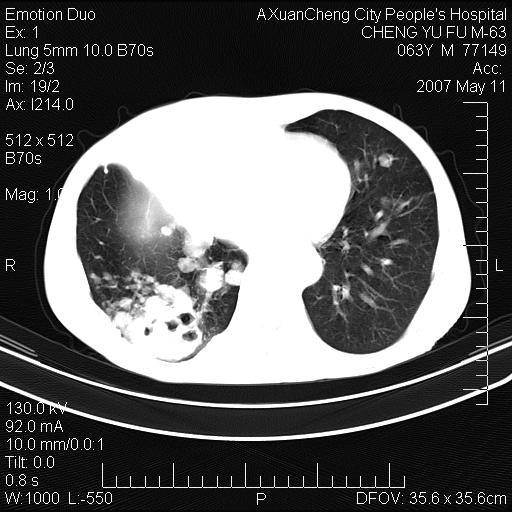

以下是引用小初学者在2007-5-11 19:32:00的发言:[br]1、首先考虑干酪性肺炎支气管播散[br]2、支气管肺泡癌待排

以下是引用zhangzhongshou在2007-5-11 19:30:00的发言:[br]细支气管肺泡癌可能性大。